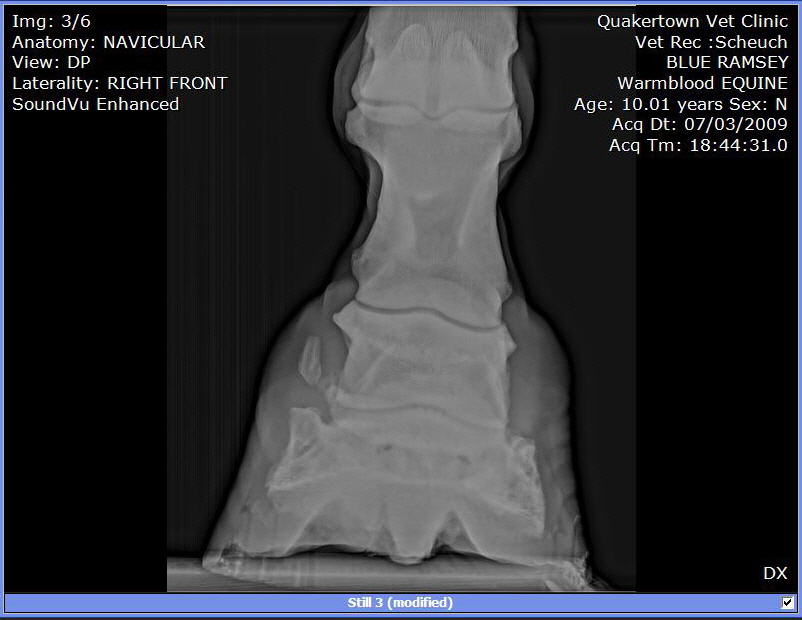

We put shoes on. Last week the farrier replaced them. He used a hoof tester checking of abscess or some reason for his slight limp. Since that day he as barely been able to walk. So, we called in the Vet to have him tested. A block in the heel helped him quite a bit. A block low in front and he was able to walk and trot without a limp.

X-rays:

I can see these are not images of a healthy hoof.

Among the many abnormalities the most important is the radiographs are clear for DJD of the coffin joint or what is often called low ringbone. No the hoof testers did not aggravate it, I suspect flexion of the joint during the exam did. You will find much information on this condition and what to expect at Diseases of Horses » Lameness » Diseases of the Lower Limb » Ringbone.

I can not read xrays to save my life, but I couldn't help feeling that this horse's foot was out of balance (from Image 3/6). I can't tell if its the way his foot is positioned on the plate, but he sure looks lopsided to me.

I would get his shoes off and get him back in balance ( to me he looks low on the outside and high on the inside. I'd be able to tell better if I could see the foot from the bottom to see which way the frog is leaning. I'd try to keep him as simple as possible at least for a few days to see how he handles being barefoot.

As rtrotter noted above the horse is either standing oddly or the foot is unbalanced from side to side in the above radiographs, careful management of balance and breakover could help this horse be as comfortable as possible.

Do the images suggest that the side bone has broken off?

No Guy it does not indicate it. Though we cannot say for sure this is a common appearance of a focal area of calcification for more on this see Diseases of Horses » Lameness » Diseases of the Hoof » Side Bone and the Collateral Cartilages.